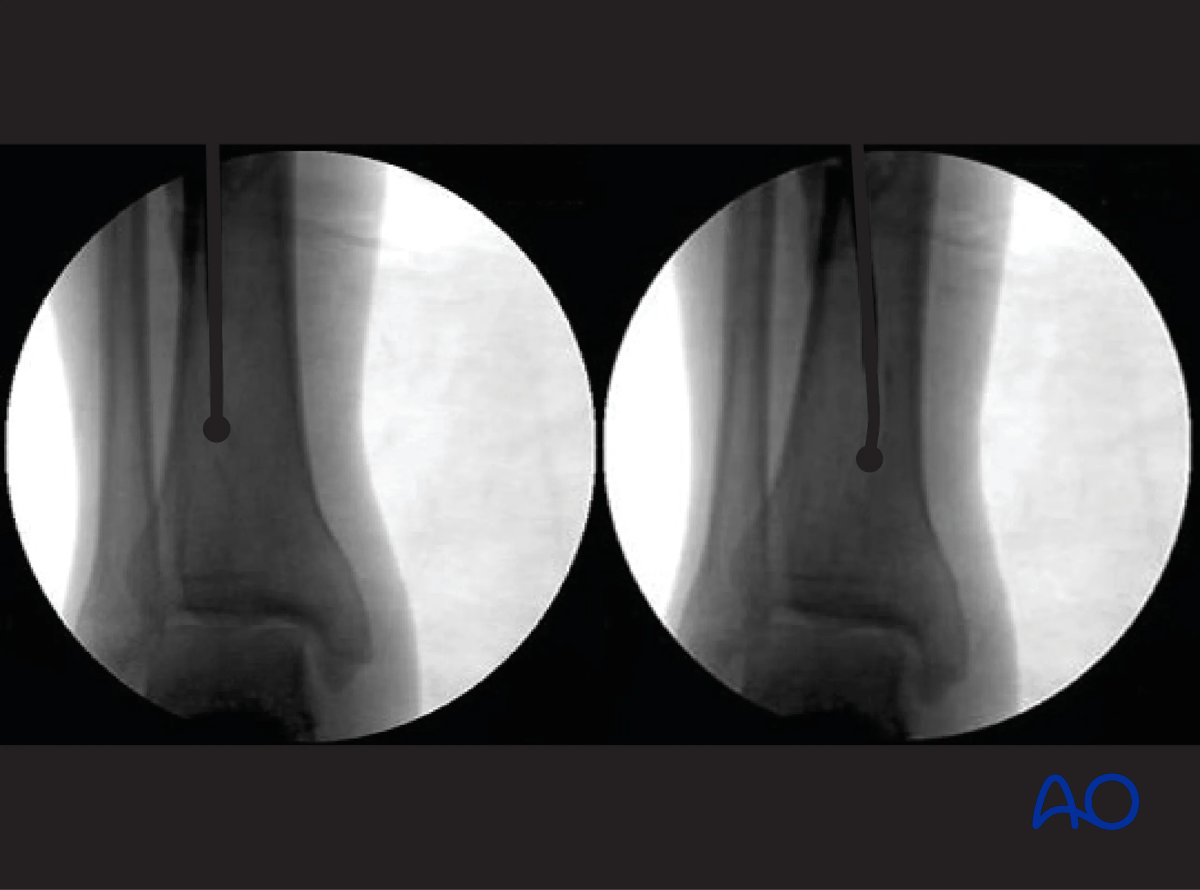

Obtaining appropriate fluoroscopic views of the proximal tibia

It is imperative to obtain appropriate AP and lateral views of the proximal tibia to ensure that the proper entry site for the tibial nail is obtained. A proper AP view has the lateral border of the tibial plateau bisect the fibular head. A proper lateral view has the femoral condyles superimposed on each other. The entry point for a tibial nail on the lateral view should be at the anterior edge of the joint line and on the medial aspect of the lateral tibial spine on the AP view.

Suprapatellar intramedullary nailing, Obtaining appropriate fluoroscopic views of the proximal tibia